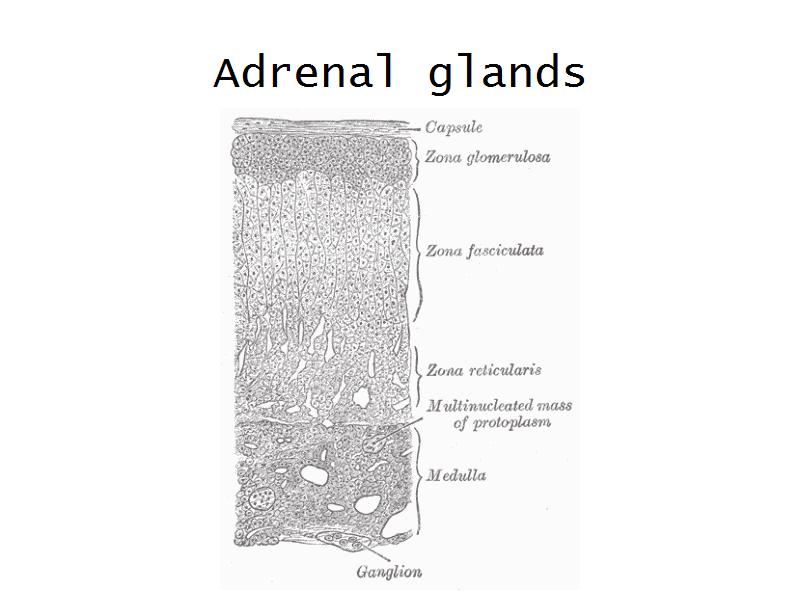

Adrenal glands

Capsule

Cortex - how many zones?

Medulla

Hormones of each?